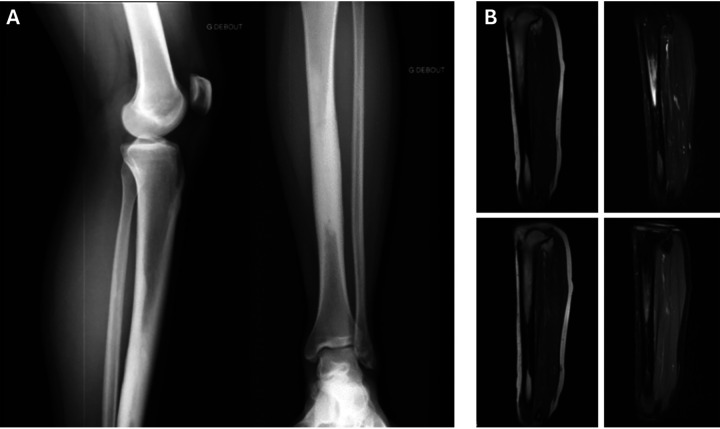

In this case, we report the usefulness of bone scintigraphy in evaluating osteoarticular pain when the diagnosis is unclear after standard morphological imaging. A 24-year-old male patient exhibited mild left tibial pain that had been intensifying over a period of 2 years. The initial radiological evaluation suggested a diagnosis of pediatric tibial bone marrow osteosclerosis associated with periostitis, based on standard radiographs and MRI. However, a complementary bone scan was required for confirmation and showed moderate hyperemia and severe hyperfixation of the tibial lesion along with similar lesions on the left femur, both humeri, and the right ulna. These new findings led to a diagnosis of Ribbing disease, a rare sclerosing bone dysplasia.